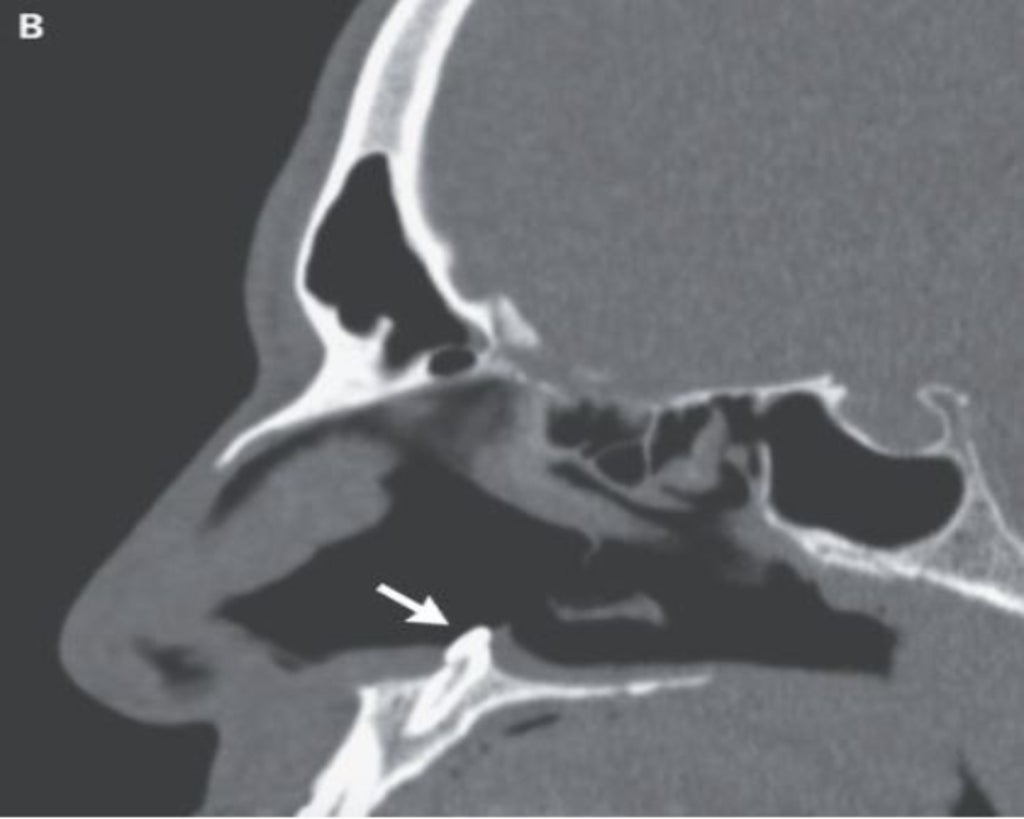

A computed tomography (CT) scan of the paranasal sinuses – or air-filled spaces that surround the nasal cavity – showed a “well-defined, radiodense mass consistent with an inverted ectopic tooth” in the right nasal cavity.

This patient’s tooth, measuring 14mm in length, was removed through surgery. The doctors pointed out that the patient’s breathing difficulty was resolved after a follow-up examination three months after the surgery took place.